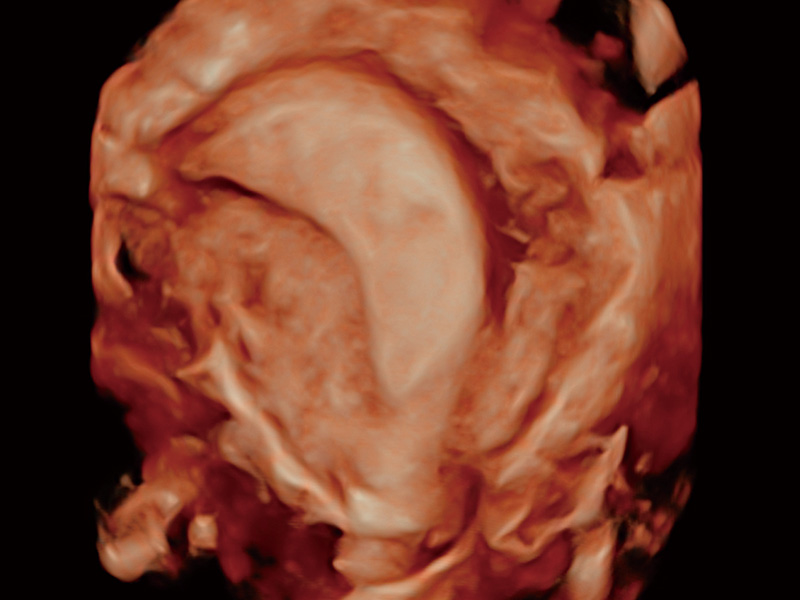

腔内三维成像技术获得显著提升,超大扇角在满足日常基础扫查的同时,支持卵泡自动测量及多种三维渲染模式,为您提供更多的诊断信息,尤其是在子宫畸形的诊断,内膜及肿瘤占位观测中起到了重要的作用。

单角子宫